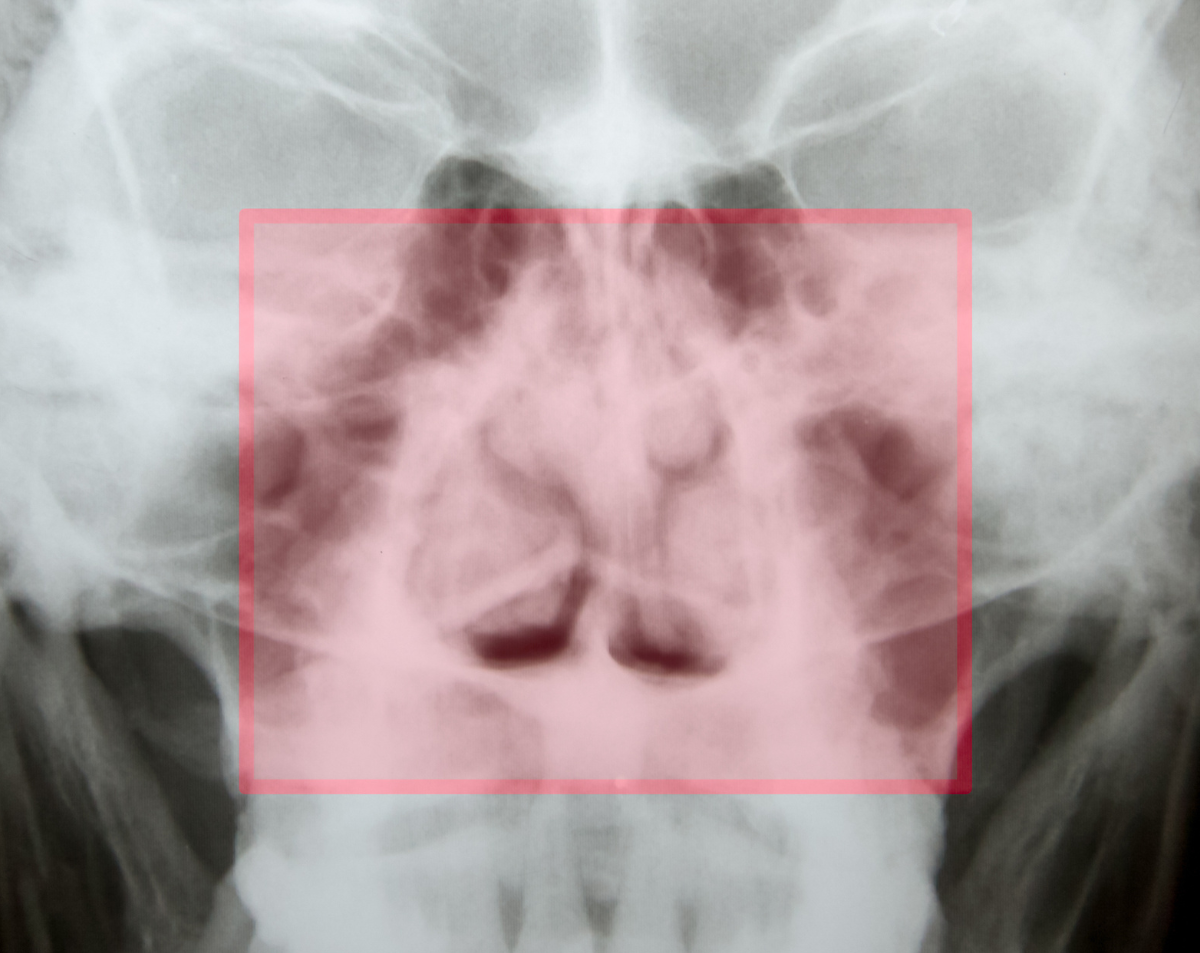

A nasal bones X-ray provides a clear view of the bones that form the bridge of your nose. Physicians often order this test after trauma, falls, or accidents to confirm fractures or bone displacement. At Desert Mobile Medical, we deliver this essential diagnostic service directly to you. With mobile X-ray technology, there’s no need to sit in crowded imaging centers—you receive the care you need in the comfort and privacy of your own space.

Why a Nasal Bones X-Ray May Be Ordered

A nasal bones X-ray is commonly recommended for:

Suspected Fractures – After a fall, accident, or sports injury.

Facial Trauma – To rule out displacement or multiple fractures.

Chronic Nasal Issues – To identify bone-related causes of breathing problems.

Congenital or Structural Concerns – To evaluate abnormalities that affect nasal passages.

Post-Surgical Monitoring – To assess healing and surgical hardware placement.

This imaging study provides quick, precise information, often serving as the first step before advanced scans like CT.